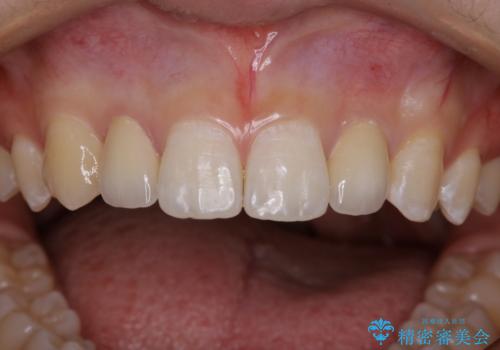

部分矯正とセラミッククラウンですきっ歯・矮小歯を効率的に治す

- 初診時、前歯部の見た目の改善を主訴にご来院されました。生まれつき歯が小さい状態の「矮小歯」とそれに伴う正中の「すきっ歯」があるため、大きなガタつきはないものの笑った時の印象に違和感が出る状態となっていました。

矮小歯が傾斜していることなどを踏まえ、より安全に治療を進めるために部分矯正を併用したセラミッククラウンでの治療を行うこととなりました。

今回のケースでは、歯が小さいだけでなく傾斜もしていたため補綴治療時に歯を削ることで神経の症状が出る可能性がありました。そのため、事前に部分矯正を行い歯軸の改善を行っておくことで、歯髄を温存することができました。